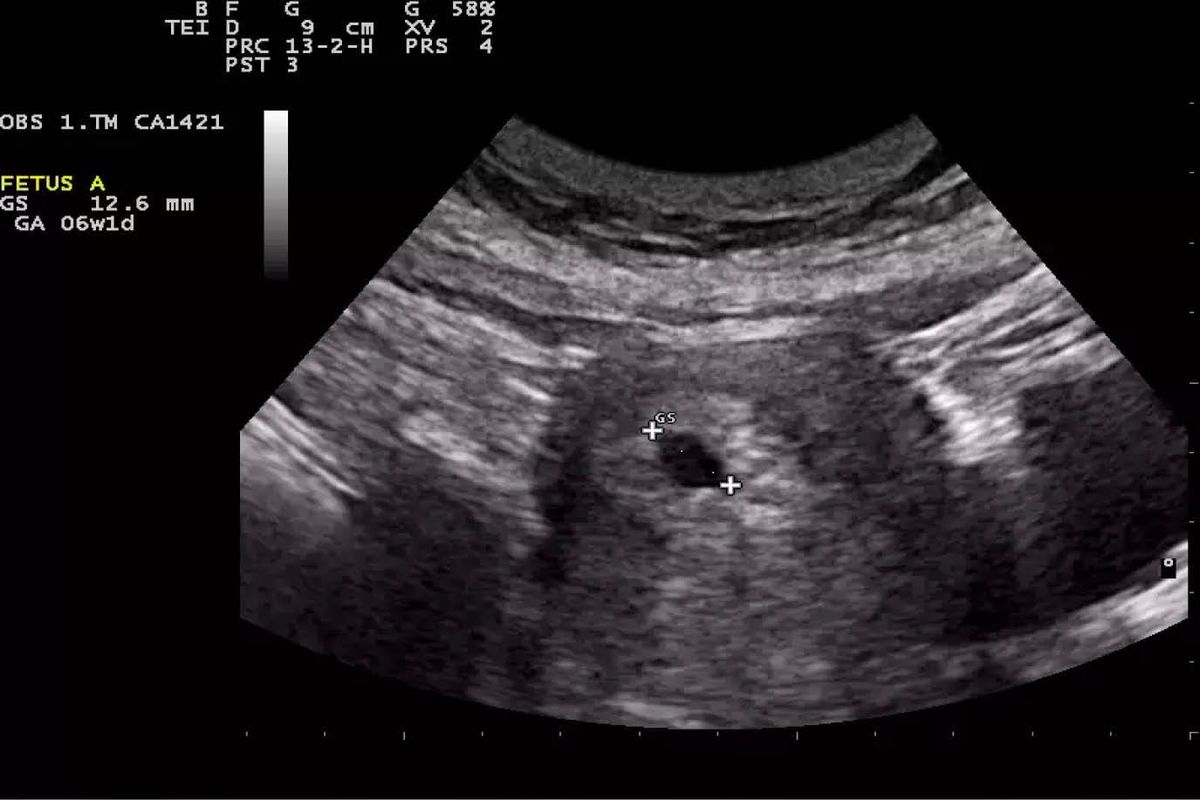

Uno de los usos más comunes de la ultrasonografía en el primer trimestre es la confirmación del embarazo y la determinación precisa de la edad gestacional. Mediante la medición del saco gestacional y el embrión, los médicos pueden calcular con precisión la fecha estimada de parto. Según el Dr. Abramowicz, esta información es crucial para el seguimiento adecuado del embarazo y para la planificación de cuidados prenatales.